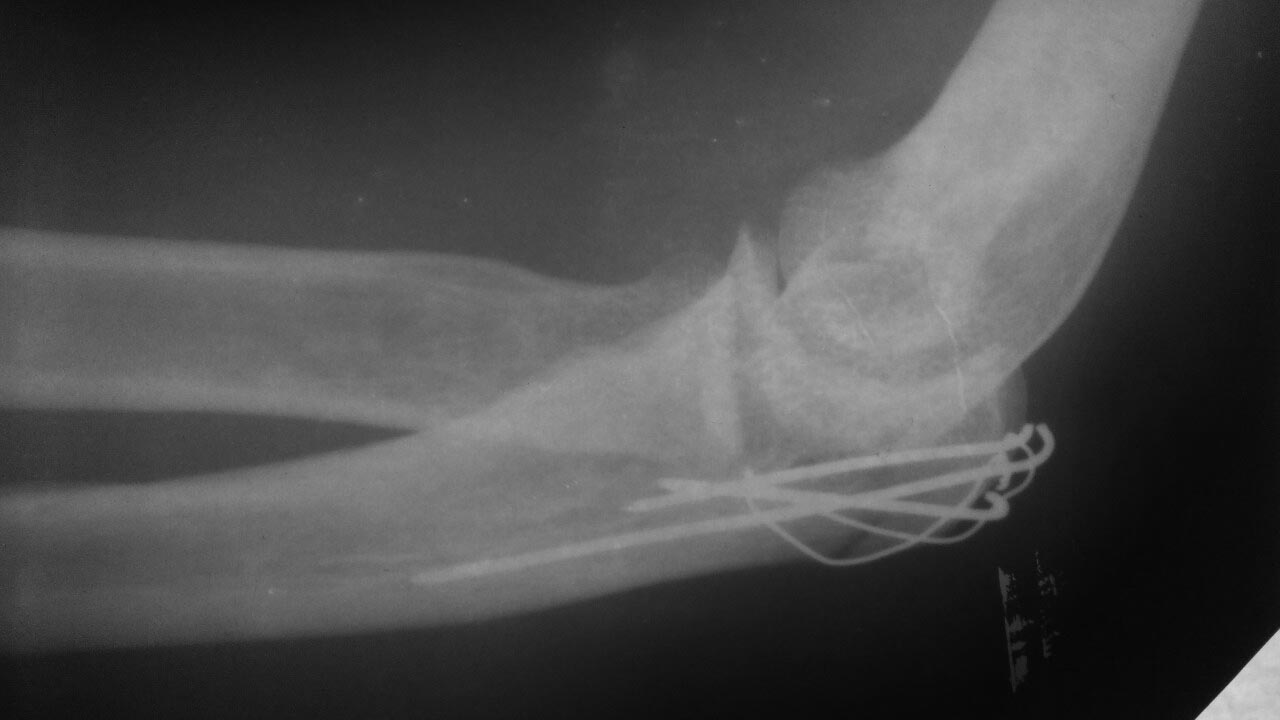

Доброго здоровья!Интересует мнение независимых специалистов по поводу проведенной операции остеосинтез спицами локтевого отростка

Разрезали локоть , поставили спицы, проволоку. на снимке после операции, видно что отломанная косточка не плотно прилегает к основной кости. Подскажите пожалуйста чем это чревато? И в Целом что вы думаете об установленных спицах и прогноз - будет ли работать сустав без ограничений( движение и нагрузки)? наложен гипс, меняют повязки на ране сейчас через день, Но спустя 11 дней после операции, отечная кисть, за ночь отечность спадает, но пока езжу на перевязку, и домой, то отек опять сильно увеличивается, это так и должно быть?

Все пока на месте.

Результат зависит не только от снимка после операции. Но и от состоятельности фиксации, т.е. от сохранения достигнутого положения фрагментов в последующий период. Надо будет сделать снимки в 4 и 8 недель после операции. И от вовремя начатой и правильно проведенной разработки движений.

Отек в таком сроке не является чем-то необычным.